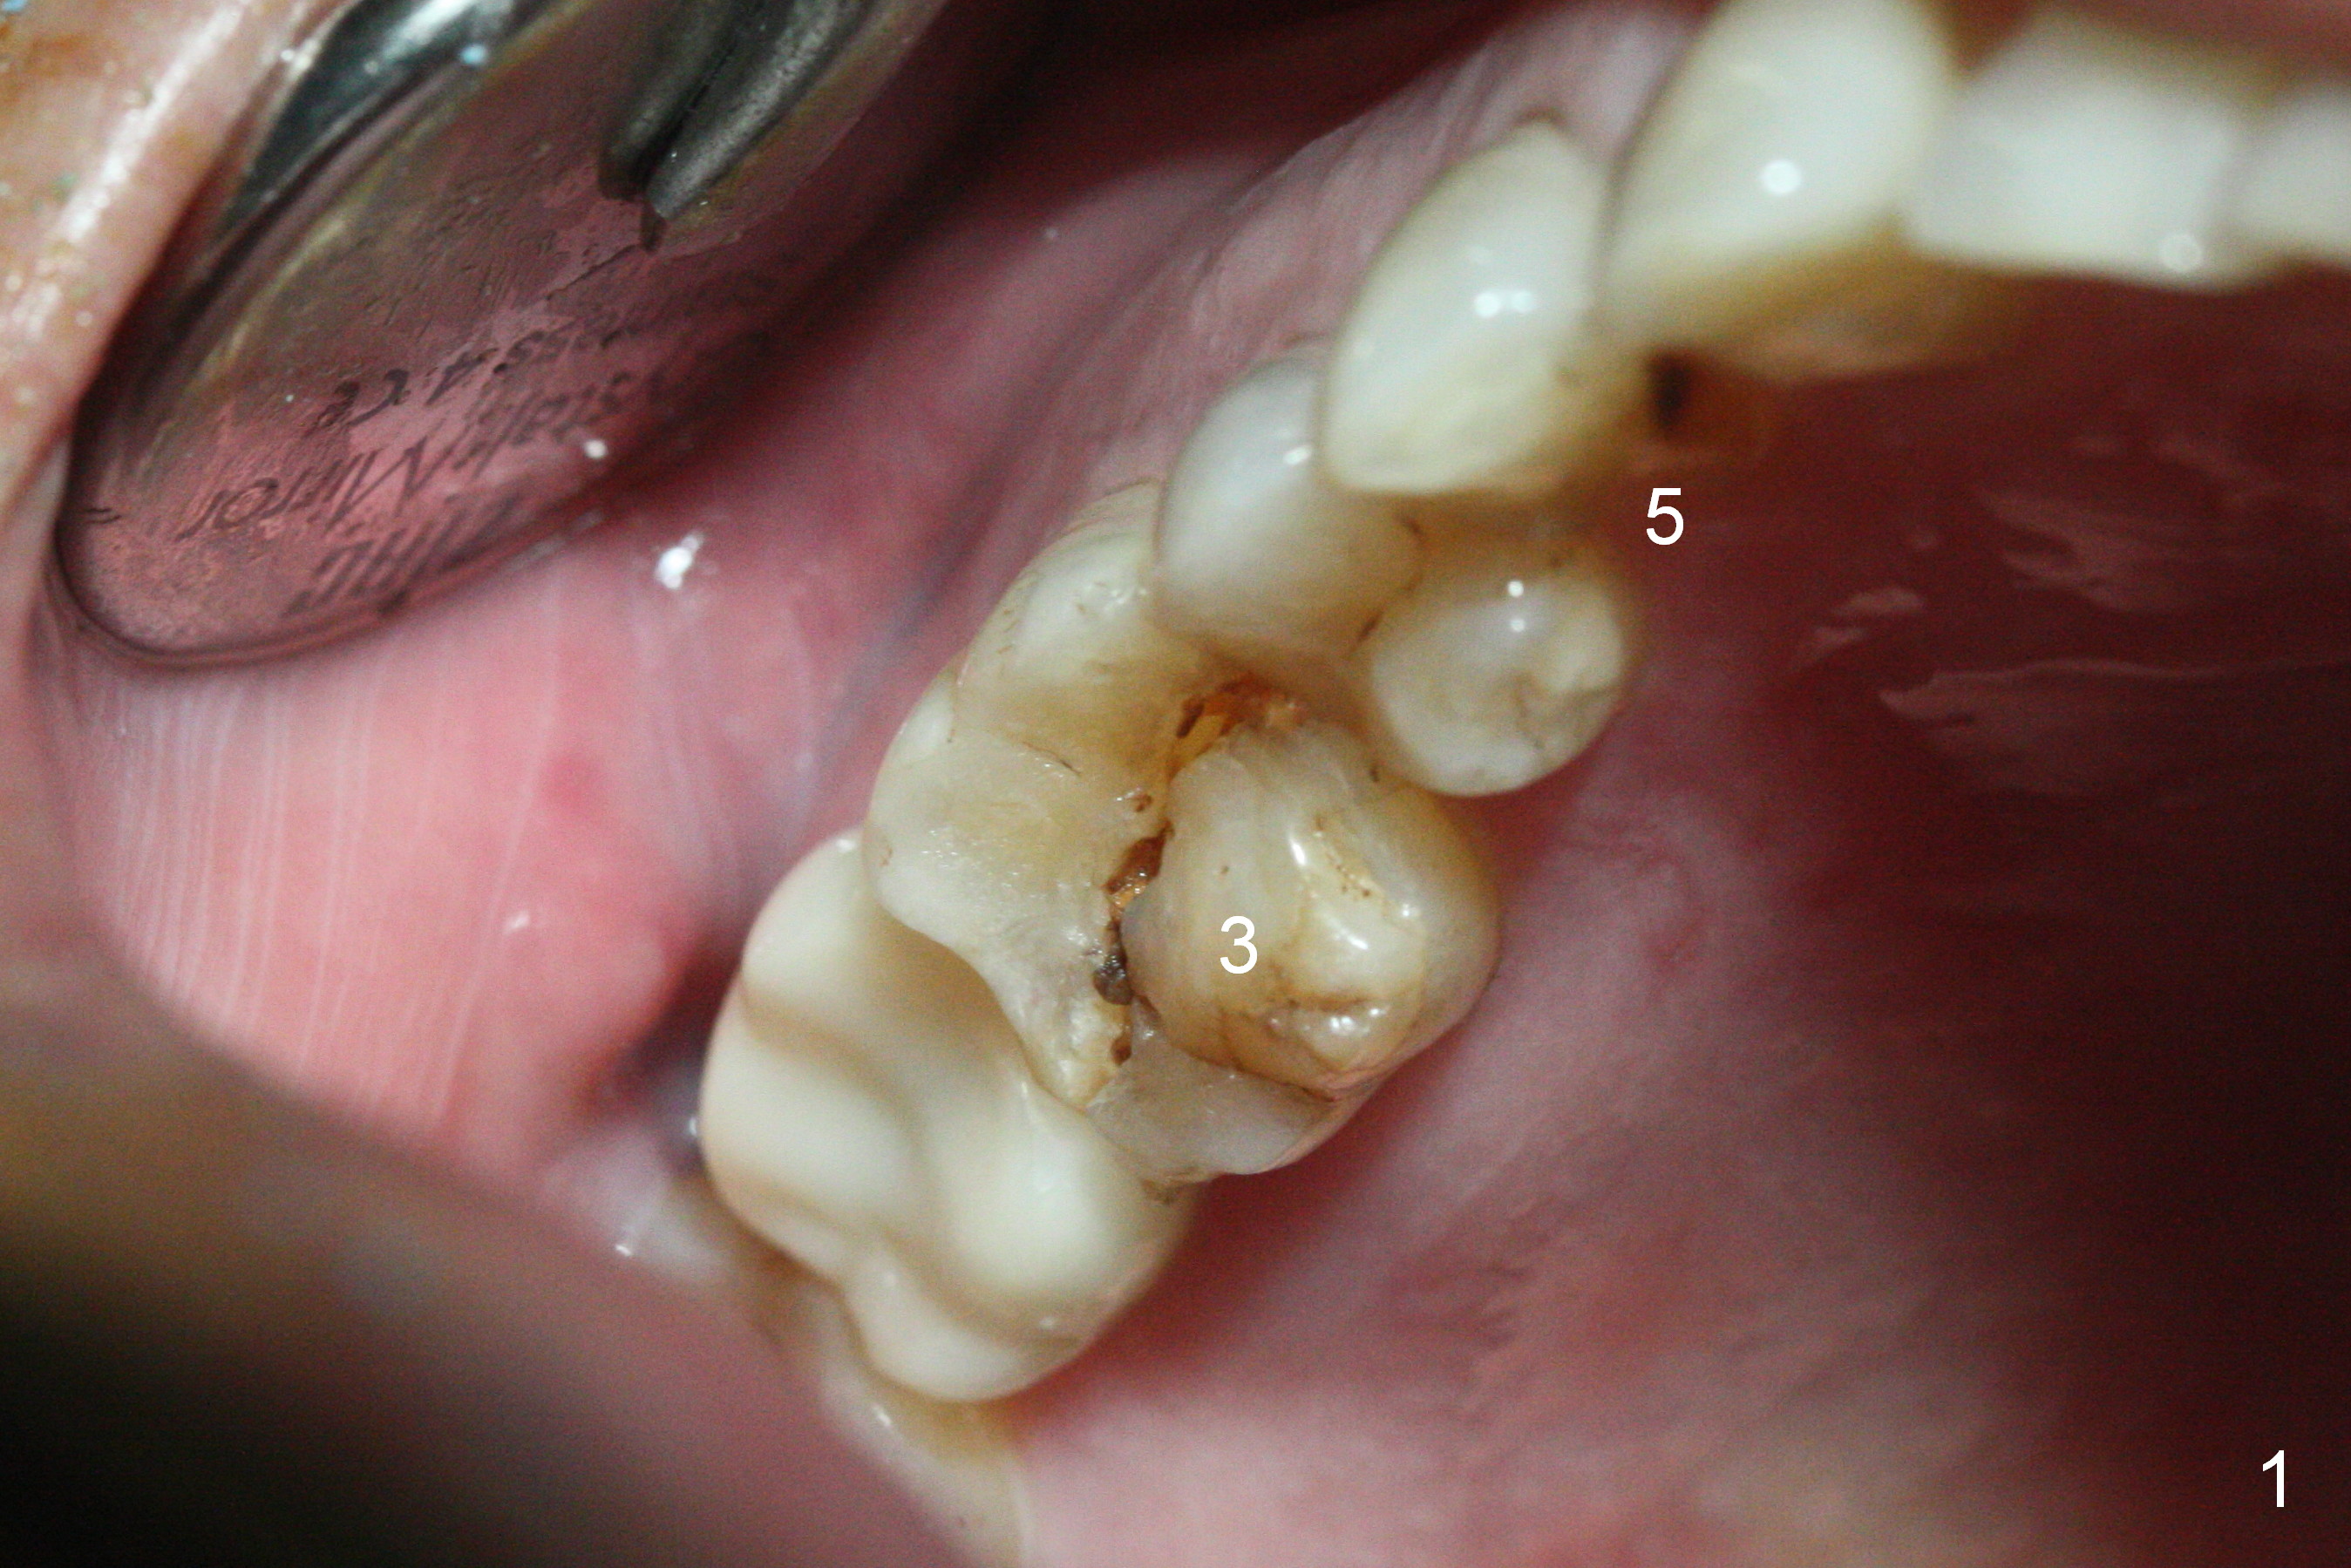

Heavy bruxism is characterized by the crack at #3 (symptomatic, requiring emergency extraction) and loss of the palatal cusp at #5 (Fig.1). Osteotomy is initiated in the septal slope (Fig.2 S) with a 1.6 mm pilot drill for 9 mm (with sudden empty feeling), followed by Marking bur. After 4.3 mm Magic Drill is used for ~ 9 mm, the sinus membrane is found to perforate. A dummy implant (5x9 mm, 2 mm shorter than design) is placed short of the sinus floor (Fig.3 ^). Prior to placement of 5.5x9 mm IBS implant (~ 35 Ncm, Fig.4,5), a piece of Osteogen plug is inserted into the osteotomy for repair of the perforation. The final implant is also shy of the sinus floor (Fig.5 ^). The Osteogen plug is apparently placed underneath the sinus floor so that it should be able to repair hard and soft tissue defects. The remaining sockets are mainly filled with Osteogen plug, while the implant plateau is covered by autogenous bone and Osteogen. When a 6.5x4(3) mm abutment is placed, an immediate provisional is fabricated (Fig.6) with its margin placed subgingival (Fig.6 inset dashed line). This innovative design of the provisional is to prevent collapse of the most coronal gingiva and loss of bone graft, particularly where the bony plate is defective. Although there is mild pain postop, nasal hemorrhage or discharge is absent.